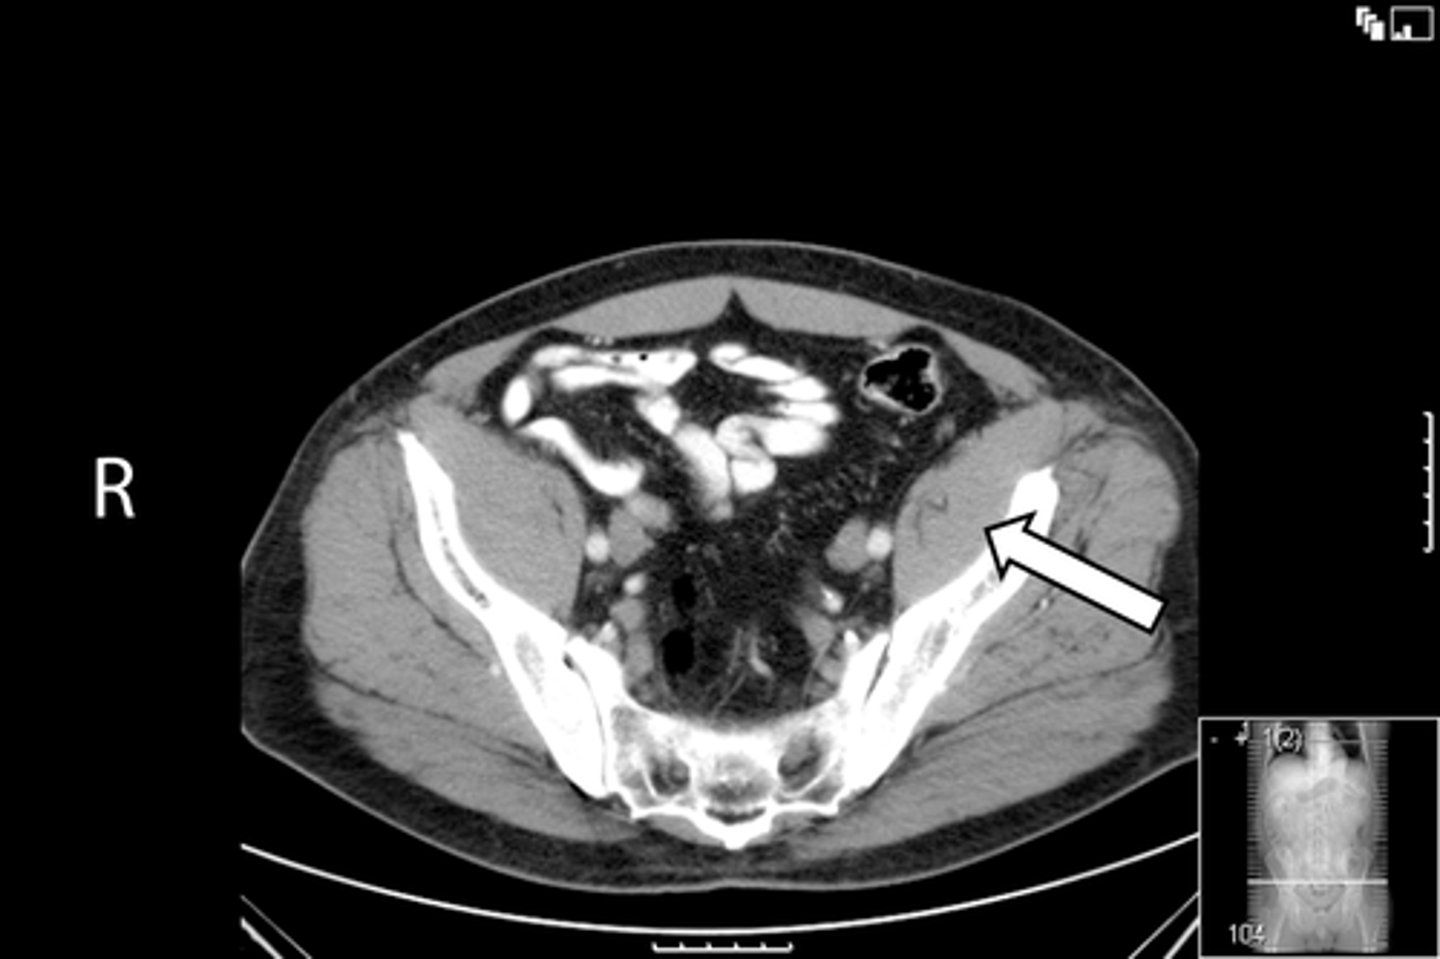

92

New cards

Axial male pelvis CT

What is the image?

<p>What is the image?</p>

93

L external iliac artery and vein

What is indicated in the image?

<p>What is indicated in the image?</p>

94

L gluteus muscle

95

L iliopsoas muscle

96

L internal iliac artery and vein

97

L sacroiliac joint

98

R external iliac artery and vein

99

R gluteus muscle

100

R iliopsoas muscle